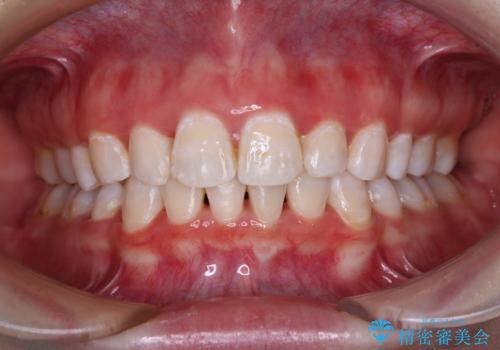

反対咬合とクロスバイトを改善して噛みやすい咬合に

- 前歯のデコボコとクロスバイトを気にして来院された患者様です。

骨格的に下顎が前方位の受け口傾向であり、それが原因でクロスバイトとなっていました。

受け口傾向の非抜歯矯正であったため、インビザラインによる矯正治療をお勧めしましたが、自己管理が面倒であるとのことで、ワイヤー装置にて行うこととしました。

なお、右奥の歯が180度回転した状態で萌出しており、こちらは改善困難なため、そのままの向きで配列することとしました。

右奥の歯が180度回転していることで、噛む度にワイヤーに無理な力がかかったようで、頻繁にワイヤーが切れてしまいました。また、下顎を後方に移動させるためのアンカースクリューも脱離することが多く、治療期間が長くなってしまいました。